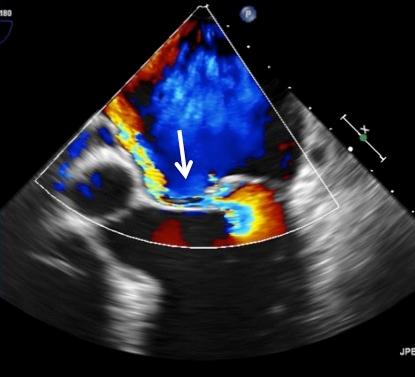

Preop Posterior Leaflet Flail (Torn leaflet) indicated by arrow, with color flow into left atrium

Diagnosis: A transesophageal echocardiogram (TEE) revealed a severely leaking mitral valve with regurgitation due to a prolapsed mitral valve.